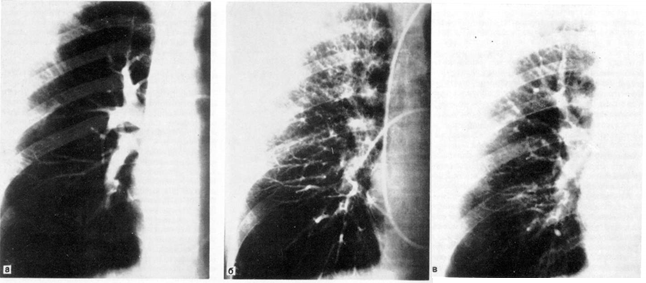

в регионах выше и ниже выявляемых анастомозов двух систем кровообращения легких. Рис. 6.

Ангиопульмонография.

а — артериальная фаза; б — капиллярная фаза; в — венозная фаза.

При анализе ангиопульмонограмм

обращают внимание на пофазовое

продвижение контрастного вещества по различным регионам легкого: легочной артерии, капиллярного русла, венозной системы малого круга кровообращения (рис. 6).

По комбинации ангиографических

признаков представляется возможным охарактеризовать вид и распространенность патологического процесса (при двухпроекционной сериографии

— посегментарно)

в легком, при этом обращается внимание на наличие деформации сосудов, смещение, контуры, разреженность сосудистого рисунка (рарефикацию),

степень развития сосудов отдельных сегментов, долей, легкого, характер расположения камер сердца, ротацию сердца и др.

При селективной ангиографии бронхиальных артерий катетер вводится в грудную аорту и далее — до устья бронхиальных сосудов; введение контрастного вещества осуществляется с помощью автоматического инъектора.

Сериография,

проводимая, как правило, в переднезадней проекции, может быть дополнена рентгенограммами в боковой или косой проекциях в зависимости от задач исследования (рис. 7).